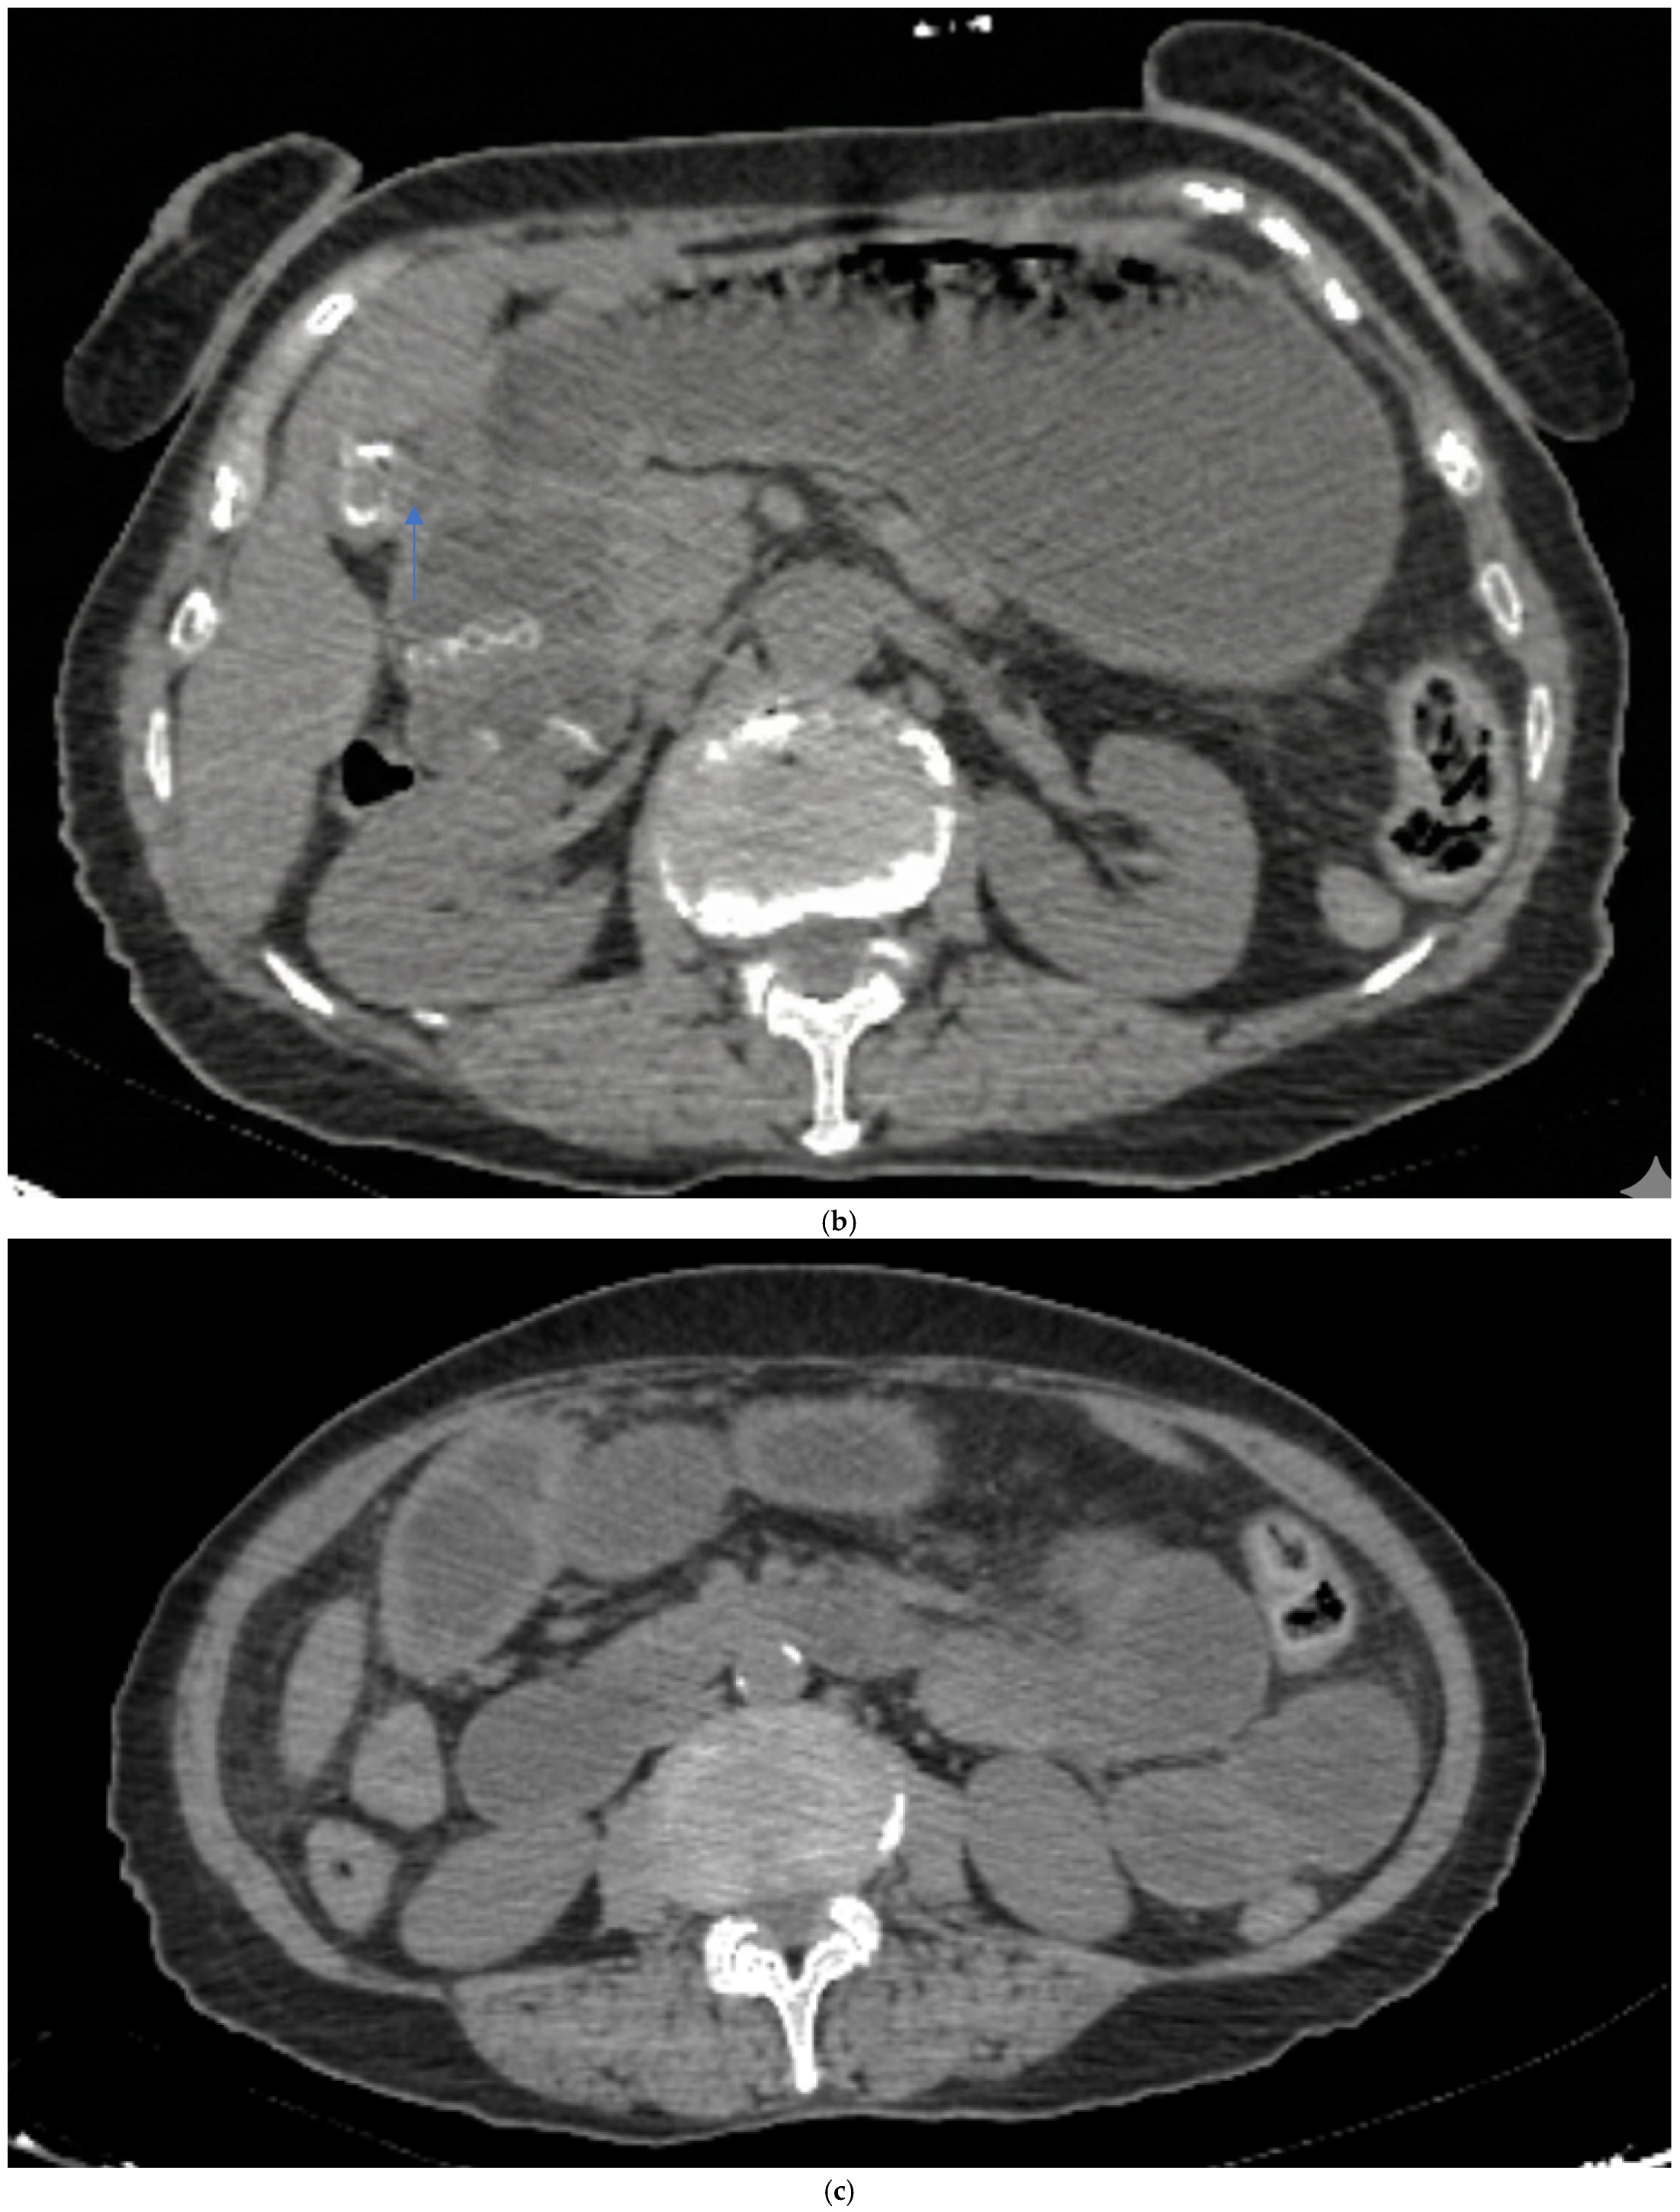

Preoperative imaging confirmed GI in all patients (Table 2). All patients had CT and plain X-ray, but none had a preoperative USG in the emergency department. CT revealed a bilioenteric fistula in all cases (12/12) (Figure 3b) and Rigler’s triad in 11/12 patients (91.7%). Air-fluid level and small bowel dilatation > 3 cm were seen in 11/12 patients (91.7%) (Figure 3c); one patient had stone impaction in the duodenum and did not show an air-fluid level. Free fluid was present in 4/12 patients (33.3%), suggesting potential peritonitis. The mean number of stones was 1.6 ± 1.2 (range 1–4), with a mean stone size of 3.19 ± 0.6 cm (range 2.6–5). The stones were primarily located in the distal ileum in 8/12 patients (66.7%) (Figure 3d). Plain X-ray showed an air-fluid level in 11/12 patients (91.7%) and pneumobilia in 2/12 patients (16.7%) (Figure 3a). Previous abdominal surgeries were found in 5/12 patients (41.67%).

Figure 3.

Radiologic images (a) plain X-ray air fluid level and pneumobilia (arrow). (b) Ct-scan bilioenteric fistula and stone (arrow). (c) ileus. (d) terminal ileum gallstone (arrow).

In our study, all 12 patients underwent CT, and Rigler’s triad was identified in 91.7% of patients, a rate substantially higher than the traditionally reported rates, reflecting CT’s superior sensitivity compared to X-ray. Small bowel dilatation exceeding 3 cm and air-fluid levels were seen in 91.7% of patients (n = 11/12); one patient with duodenal stone impaction did not show an air-fluid level. In our series, 66.7% of stones were located in the distal ileum, consistent with the literature. Only one patient had a stone impacted in the duodenum, representing Bouveret’s syndrome, which accounts for less than 10% of GI cases [4]. None of our patients underwent preoperative USG, which aligns with current practice favoring CT in emergency presentations.